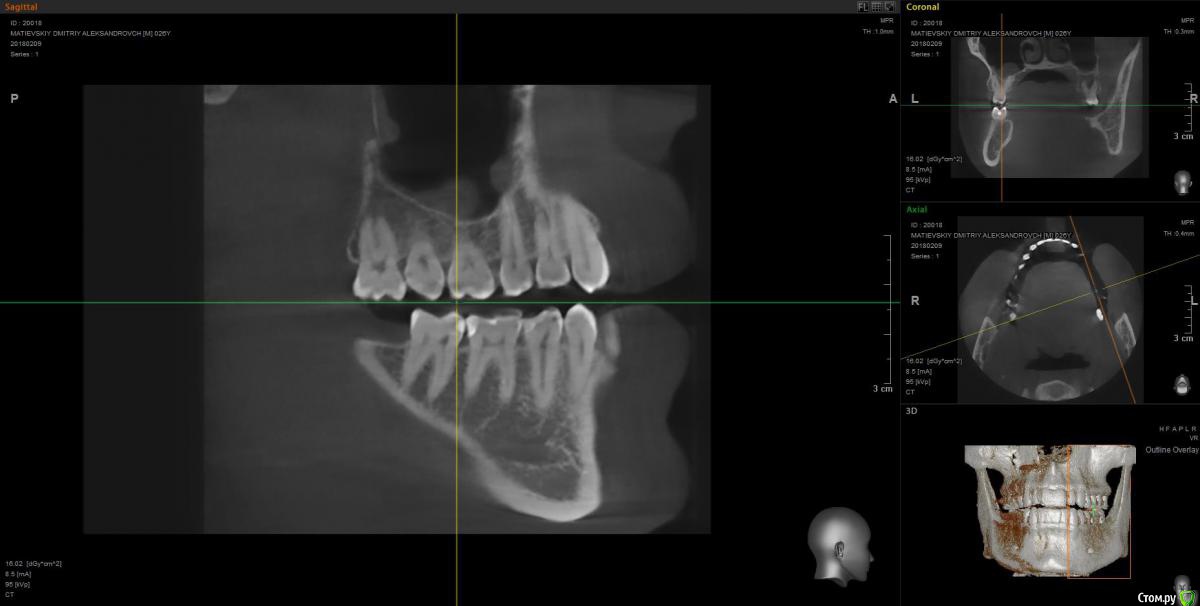

Dmitry91 Опубликовано 13 февраля, 2018 Поделиться Опубликовано 13 февраля, 2018 Добрый день, уважаемые доктора и знатоки! Прошу вашей помощи или мнения по ситуации. Есть проблемный 6й зуб на правой нижней челюсти с огромной пломбой на штифте.Внизу у корней круглые образования (кисты). Под пломбой, похоже, кариес. Стоит ли удалять зуби ставить имплант? Или есть возможность сохранить зуб? Что посоветуете? Если имплант, то какой лучше? Второй вопрос. Нужно ли удалять верхние зубы мудрости (нижних нет)? Похоже рядом с ними на 7ках естьконтактный кариес из-за того, что между зубами мудрости и 7ками застревает пища. Приложил скрины КТ и само 3D КТ в архиве, ссылка ниже. https://yadi.sk/d/kfX43ds43SMxCo Если нужно посмотреть фото с другой стороны, могу сделать. Кто поможет, заранее спасибо!) Ссылка на комментарий

Irouil Опубликовано 13 февраля, 2018 Поделиться Опубликовано 13 февраля, 2018 Удалять восьмерку (вижу только одну) - ОБЯЗАТЕЛЬНО! Удалять шестёрку? Я перспективы лечения не вижу. Какой имплант ставить? Самый надёжный, без оглядки на эстетику. Ссылка на комментарий

DmitrySH Опубликовано 13 февраля, 2018 Поделиться Опубликовано 13 февраля, 2018 ? Или есть возможность сохранить зуб? Если хотите гарантий, то удаляйтеЕсли есть желание сохранить зуб, то можно перелечить. Очаги воспаления скорее всего пройдут, но зуб будет достаточно хрупкий и ненадежный. Соответственно без гарантии. А по стоимости примерно равносильно имплантации Ссылка на комментарий

колесников Опубликовано 14 февраля, 2018 Поделиться Опубликовано 14 февраля, 2018 6ка удаляется. Желательно одномоментно поставить Имплант. Рекомендую Astra tech. Из дополнительных манипуляций будут:формирователь,0,5г костного материала, пластика десны. Верхняя восьмерка ,с этой стороны , так же удаляется. Ссылка на комментарий